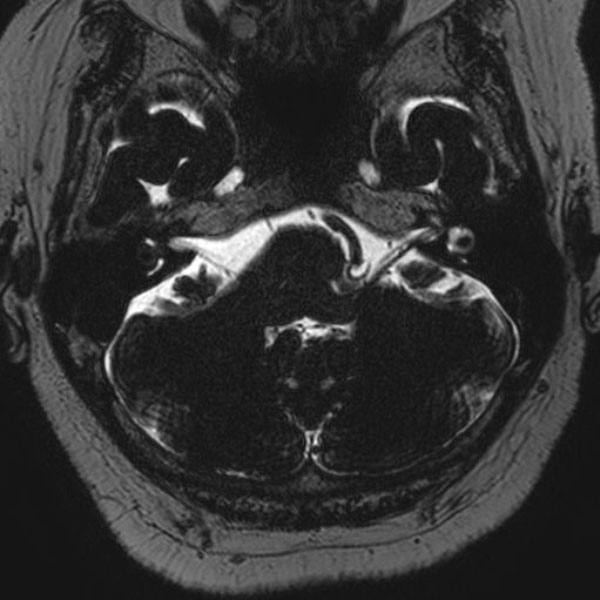

手術前

(MR1)